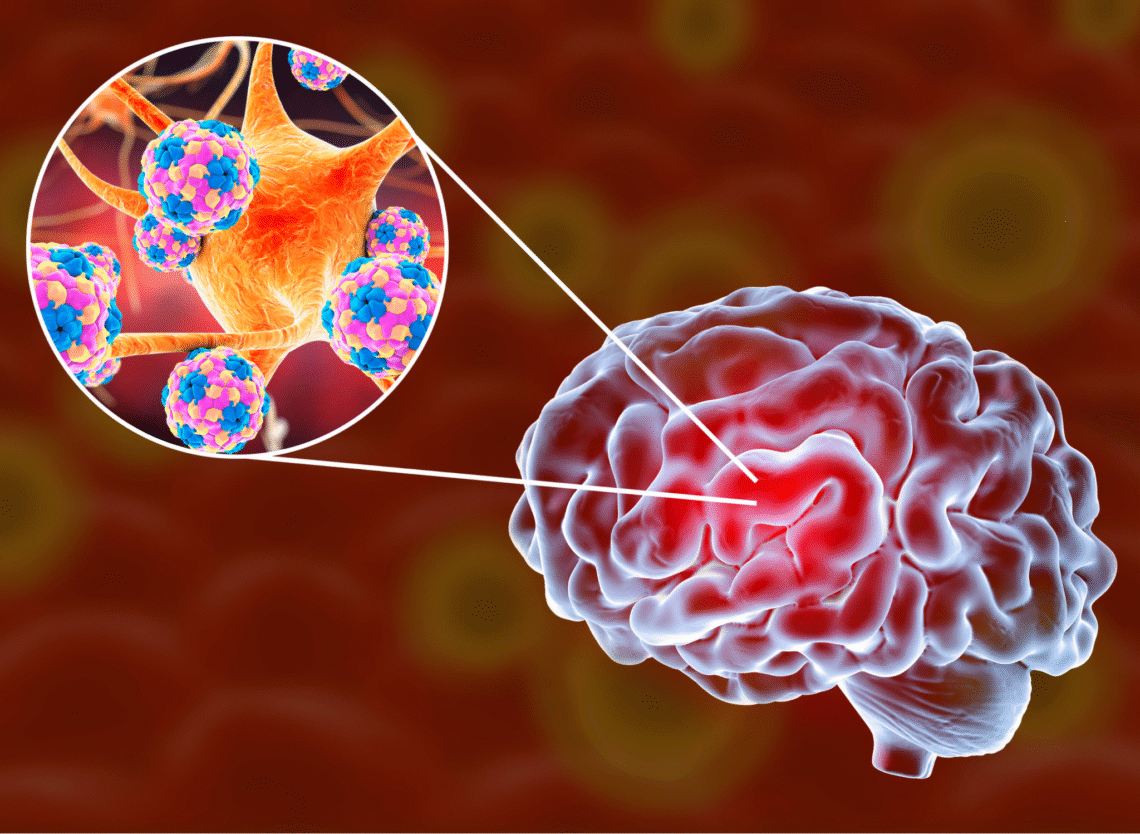

La meningitis continúa siendo una de las infecciones más graves del sistema nervioso central. Según la Fundación Meningitis Progress Tracker, cada año se registran casi 2,3 millones de casos en el mundo. La meningitis bacteriana resulta especialmente preocupante. La Organización Mundial de la Salud (OMS), advierte que alrededor de 1 de cada 6 personas que la contraen mueren y 1 de cada 5 presenta complicaciones graves.

Se denomina meningitis a la inflamación de las membranas (meninges) que cubren y protegen al cerebro y a la médula espinal. Una infección viral o bacteriana del líquido que cubre y circula por estas membranas ocasiona esta hinchazón. Sin embargo, otros factores también pueden causar inflamación de las meninges como traumatismos, cáncer, ciertas drogas o medicamentos u otro tipo de infecciones (parásitos, amebas, hongos).